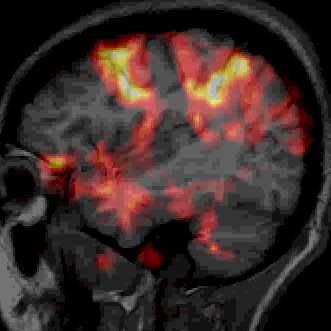

The alpha-blending of two images loaded into the same MIPAV frame can be adjusted to that only one or the other of them is visible, or anywhere in between. Different lookup tables (LUTs) can be applied to each data set to make differences in the two images more apparent.